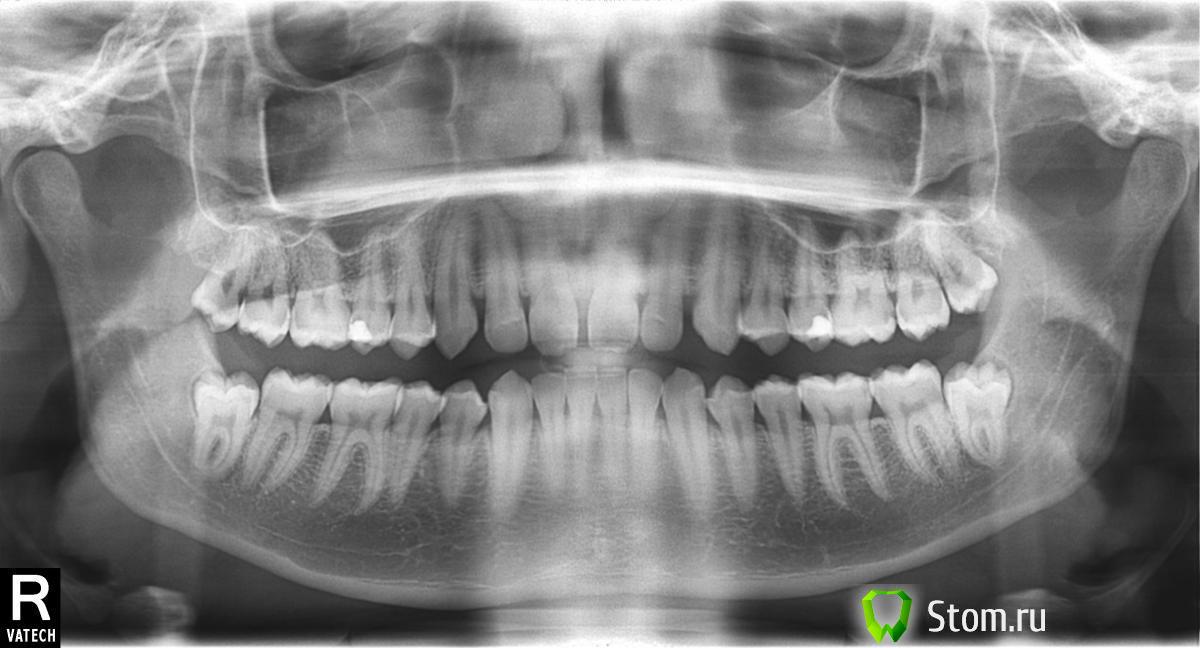

Здравсвуйте. Мне 23 года. Наконец-то руки добрались до кривых зубов. Цель была выпрямить зубы, убрать тремы, ну и заодно выпрямить прикус. Ортодонт на приеме сказал, что прикус у меня ужасный, что из-за него у меня впоследствии (лет через 10) будут большие проблемы с парадонтом, которые уже начались сейчас судя по снимку. Теперь меня забеспокила уже другая проблема. Два центральных нижних зуба у меня действительно немного шатаются уже сейчас. Действительно ли у меня настолько ужасный прикус, что из-за него через несколько лет зубы начнут еще больше шататься? Или же дело вовсе не в прикусе? И прокомментируйте пожалуйста парадонт на снимках тоже. Спасибо.

Основная нагрузка при функции приходится на фронтальные зубы, отюда подвижность и стираемость. Возможные проблемы с пародонтом могут быть связаны именно с неправильной нагрузкой. Правильное ортодонтическое лечение поможет решить вашу проблему, неправильное - ухудшит.